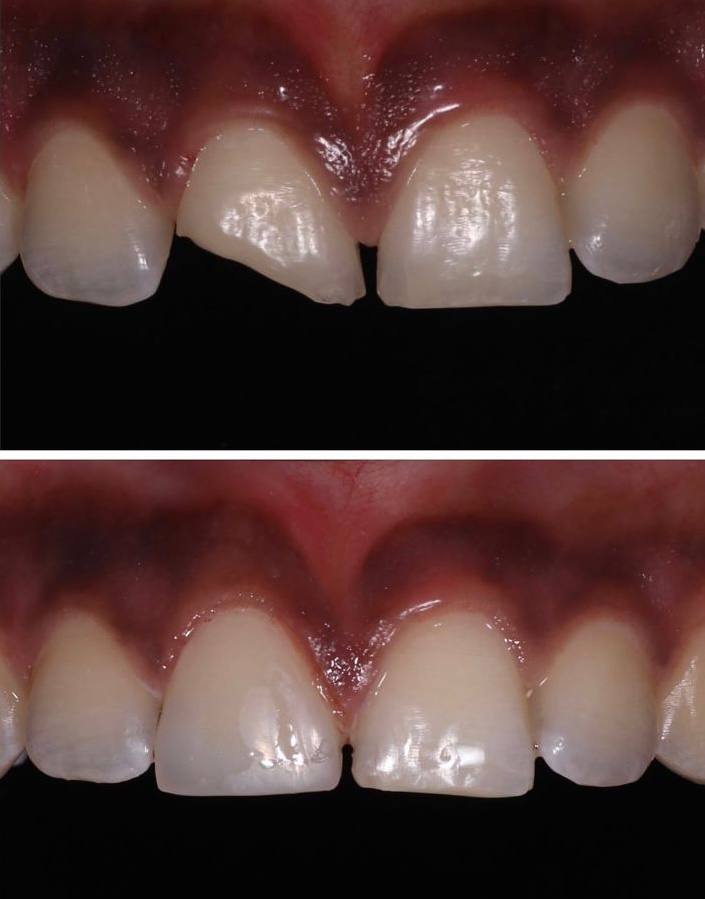

Estética Dental

Transforma tu sonrisa con tratamientos diseñados para resaltar tu belleza natural. Ofrecemos blanqueamientos, carillas y remodelación dental para lograr una sonrisa armónica, saludable y atractiva.